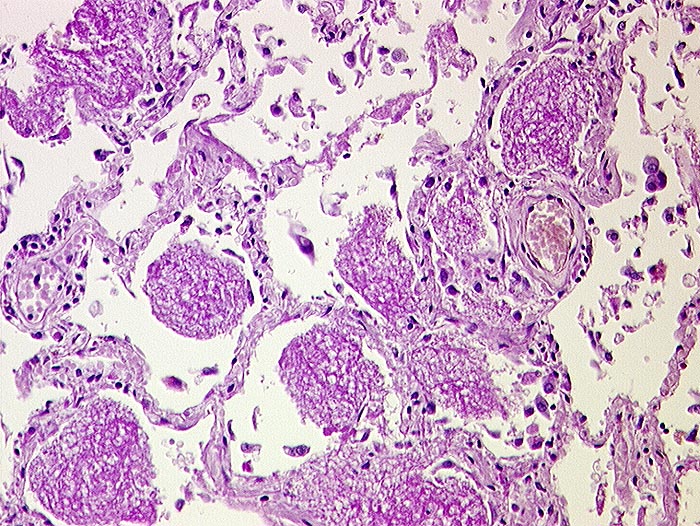

Pneumocystis jirovecii Pneumonie

Lunge

Wabiges, körnig schaumiges intraalveoläres PAS-positives erregerhaltiges Material. Wegen Immunsupression nur gering ausgeprägtes interstitielles entzündliches Infiltrat. In dieser Färbung sind keine Erreger erkennbar.

Immunsupressive Behandlung wegen Systemvaskulitis.